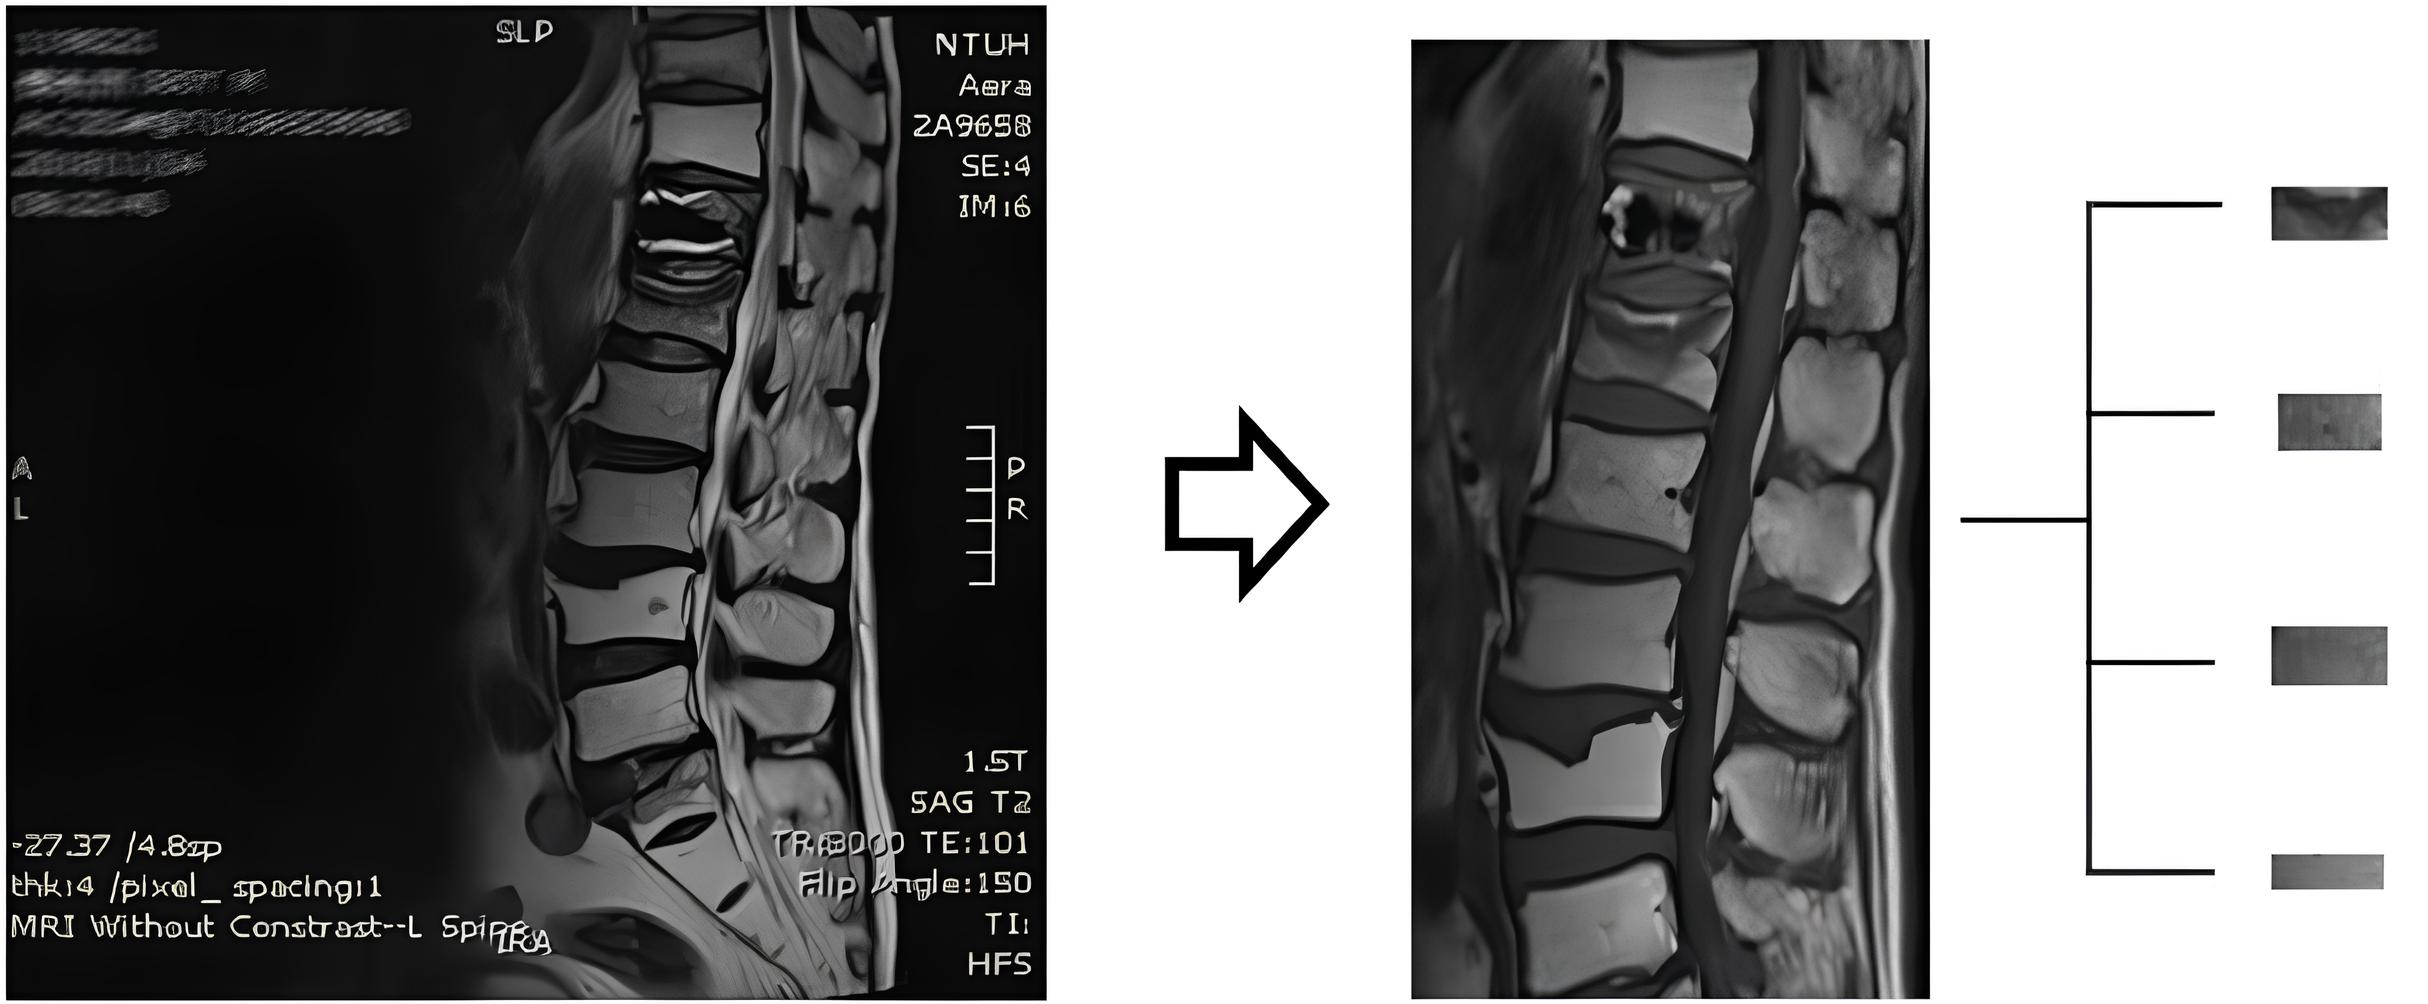

All patients underwent 3T Magnetom Verio MRI systems (Siemens Healthcare, Erlangen, Germany) and T1-weighted and T2-weighted MRI images were used in this study. The sagittal midline image of a single vertebra was segmented from an MRI image as a sample in the dataset. Four vertebrae (first to fourth) of the lumbar spine, which were comparatively evaluated to determine their BMD, were segmented (

Figure 1). However, vertebrae with compression fractures that could potentially introduce bias to the BMD calculation were excluded. A total of 738 T1-weighted and 738 T2-weighted images of vertebrae generated from 218 patients were collated for analysis. T1-weighted and T2-weighted images were used separately to generate different prediction models.